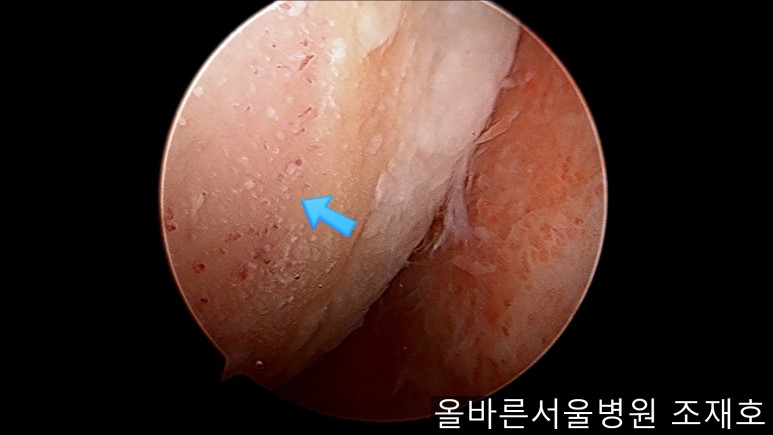

通过关节镜图像可看到:由于内侧股骨髁软骨损伤骨头已经显露出来。

胫骨上端的软骨损伤严重,也露出了骨头。

正是缺失软骨的部位碰到一起,引发剧烈疼痛,腿部逐渐变形。